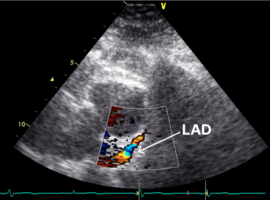

Clinical Cardiology Case Report

The Journal offers case reports in clinical cardiology, images, case series and heart surgery videos to publish. original research, research articles, review articles, case studies, commentaries, short communication, and Letters to the heart problem, heart and blood vessel disorders, cardiovascular diseases, myocardial infarction (heart attack), issues of cardiac arrest, stroke, techniques and procedure used in stent implantation, anticoagulant drugs (blood thinners), basic research in heart structure and functions and other medical conditions and associated treatments is aiming to stand out and publish remarkable findings in the major areas of cardiovascular medicine emphasizing on diagnostic, therapeutic and disease management sections.